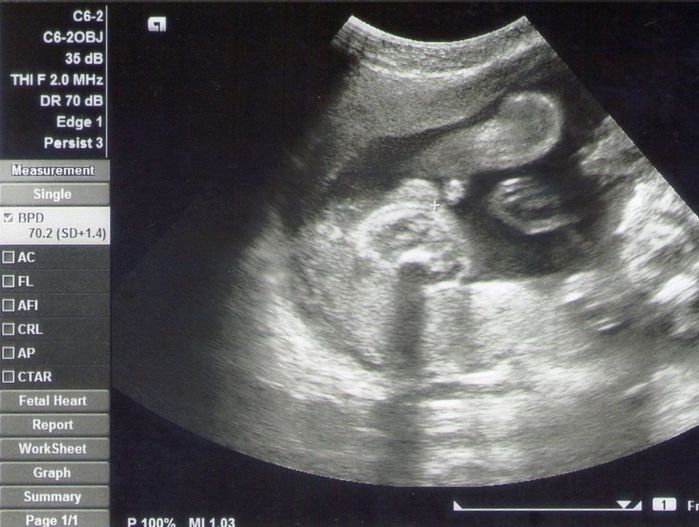

妊娠26週目のエコー写真 性別判明

毎日おなかの中で活発に動くようになってきました。今週のエコーで男の子だと判明しました。エコー画像の上側に足があり、その下の小さく丸く写っているのが男の子のシンボルです。胎児ネームを「ベビオ」にして、呼びかけることにしました。夫と一緒に、市が主催しているパパママ教室に行きました。10㎏の重りをつけた夫は、「妊婦さんって大変だな~」と感じたようでした。